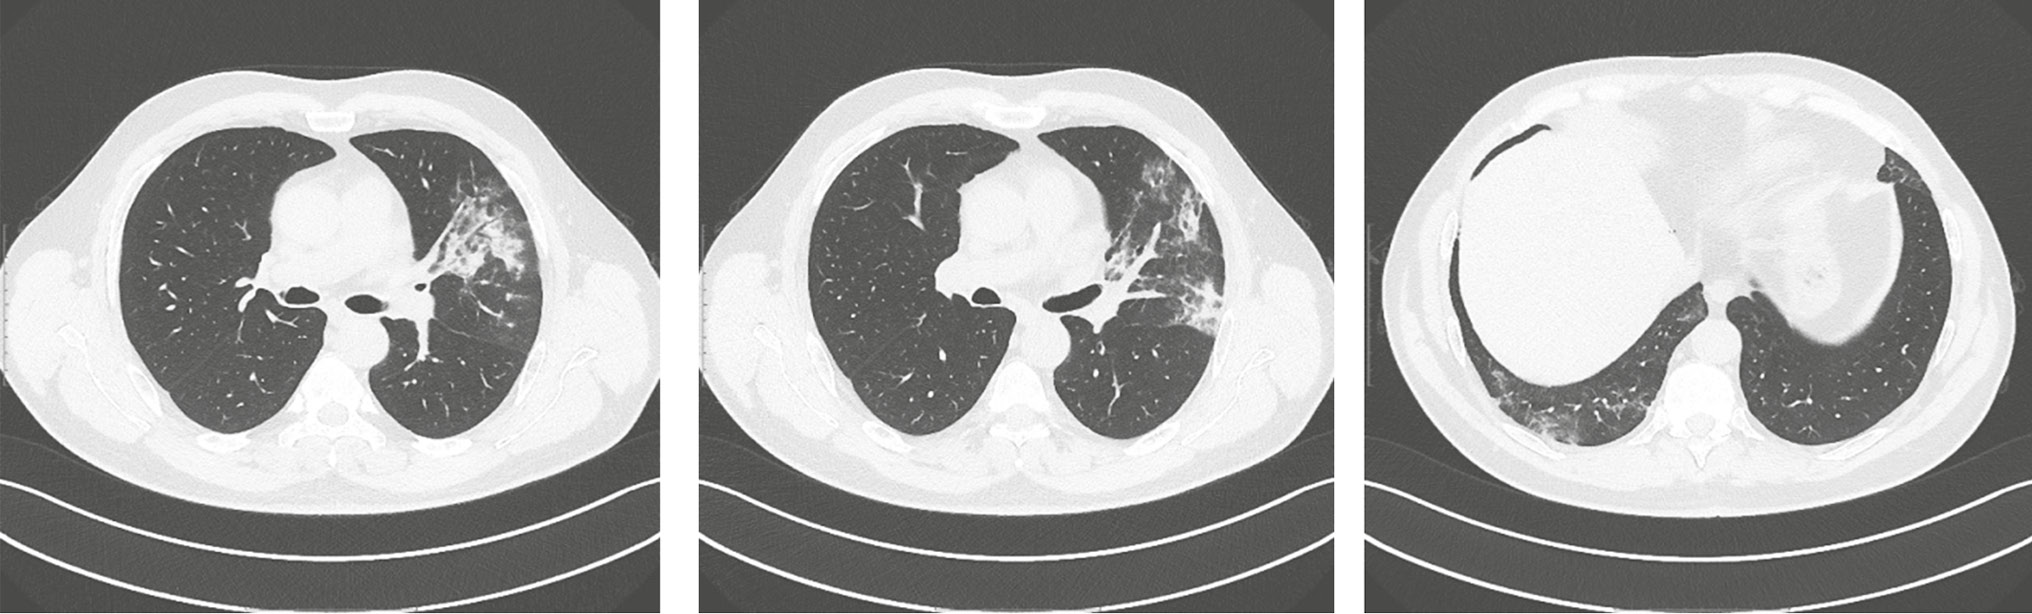

Контрольные исследования на 5-е и 7-е сут стационарного лечения мазка со слизистой оболочки ротоглотки методом ПЦР не выявили наличие РНК вируса SARS-CoV-2. Результаты КТ органов грудной клетки от 24.04.2020 продемонстрировали положительную динамику, уменьшение очагов «матового стекла» (рис. 2). Учитывая стабильное состояние пациента, отсутствие лихорадки и лабораторные маркеры острой воспалительной реакции, а также двукратный отрицательный результат ПЦР на РНК SARS-CoV-2, на 10-е сут стационарного лечения пациент был выписан на амбулаторное долечивание с рекомендациями продолжить иммуносупрессивную терапию под контролем концентрации препарата.

Рис. 2. Пациент, 54 года: данные компьютерной томографии органов грудной клетки от 24 апреля 2020 г. на фоне лечения